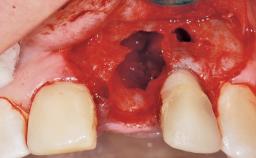

Immediate Flapless Placement of an Implant in a Maxillary Left Central Incisor Site

A 42-year-old female patient was referred to our clinic at the School of Dentistry of the University of São Paulo in November 2004, presenting a deficient restoration in the upper left central incisor. The clinical examination revealed no gingival retraction or any signs of gingival inflammation and, therefore, previous periodontal treatment was not considered. The patient presented a high lip line at full smile and a thin tissue biotype. This combination characterized a high-risk situation from an anatomic point of view, which required careful preoperative planning and cautious surgical execution.

Soft Tissue Anatomy Intact Defective

Bone Volume Horizontally and vertically sufficient Horizontally deficient Deficient vertically or deficient vertically AND horizontally